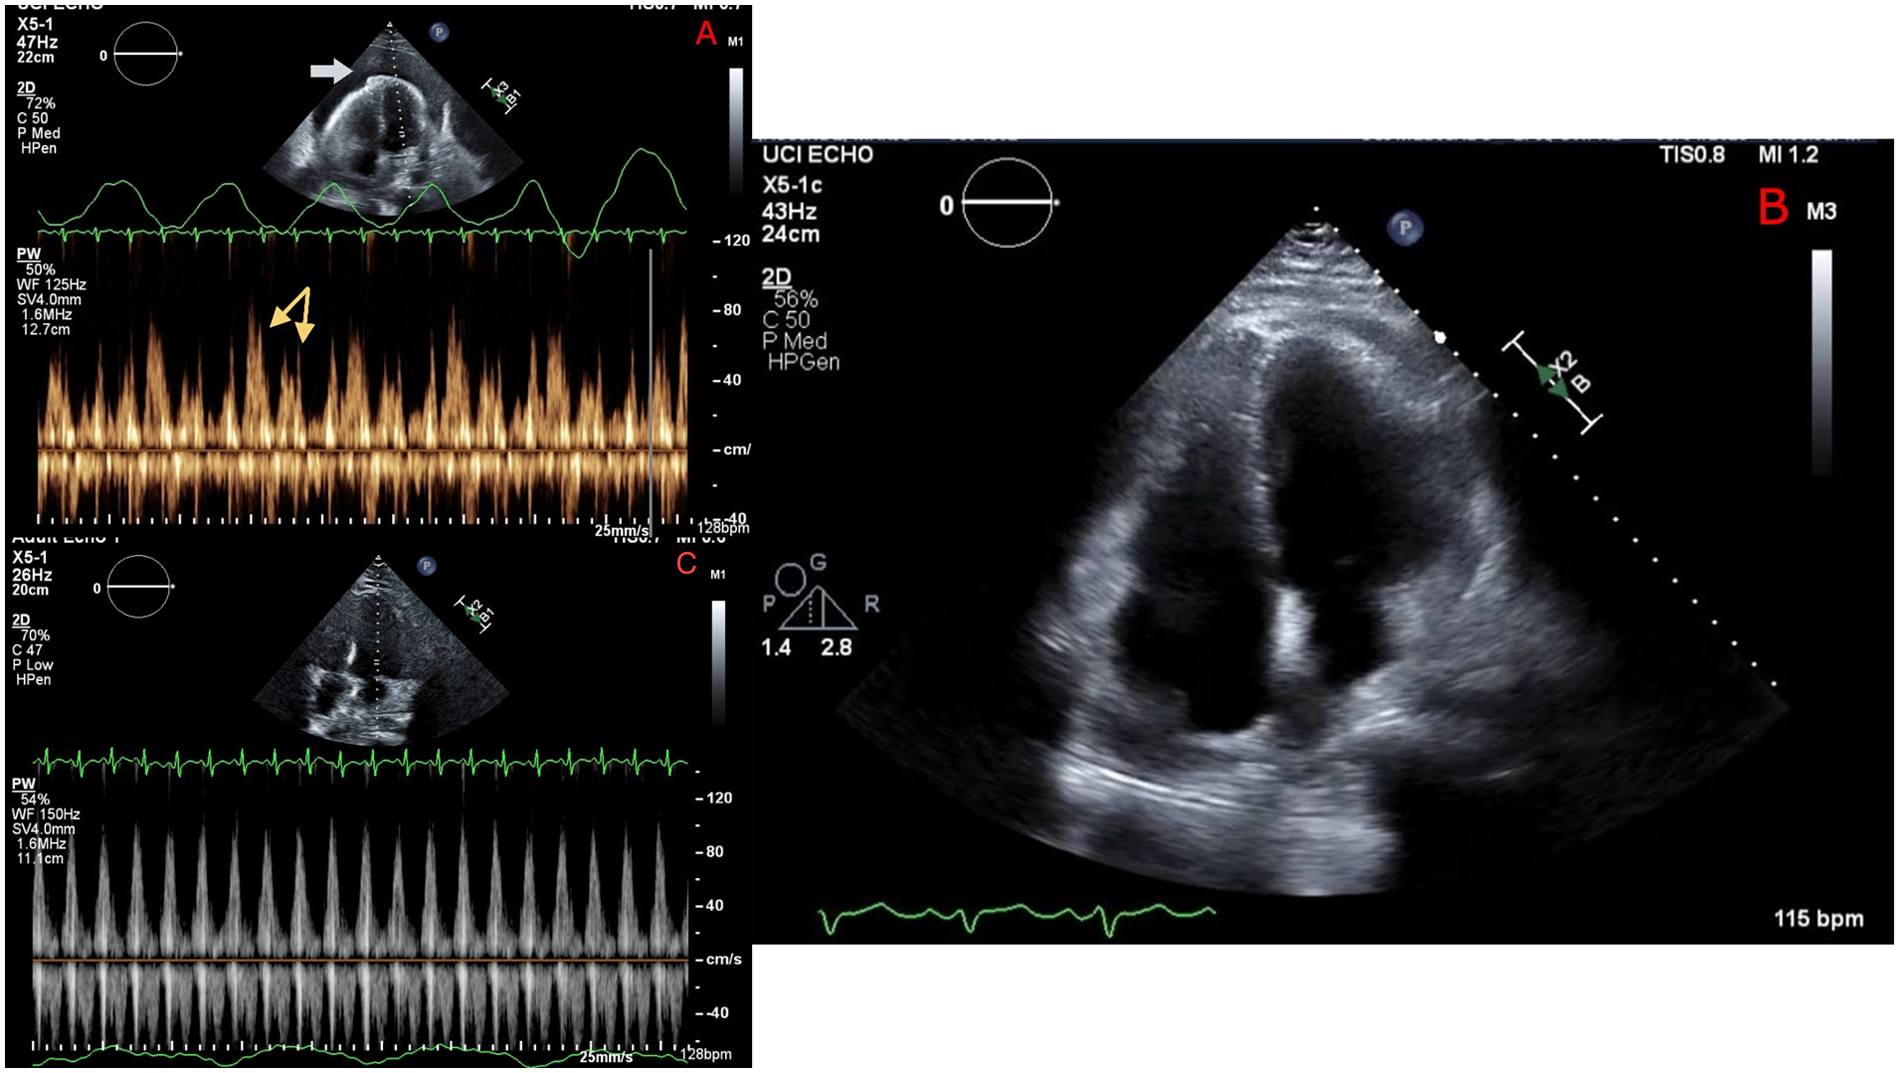

An echocardiogram demonstrated a large pericardial effusion, inversion of the right ventricular (RV) wall in early diastole, ventricular interdependence, significant respiratory variation in mitral and tricuspid inflow velocities, and a plethoric inferior vena cava (IVC), which were all concerning for tamponade physiology. A chest computed tomography (CT) was remarkable for a large anterior mediastinal mass abutting the pericardium, which was deemed to most likely represent a germ cell tumor, although lymphoma could not be definitively excluded on imaging alone. The patient received emergent pericardiocentesis and drain placement with evacuation of 650 ml of sanguineous fluid, successfully reducing pericardial pressure from 28 to 5 mmHg. A repeat echocardiogram showed a resolution of the pericardial effusion and a resolution of RV wall inversion and respiratory inflow velocities (Figure 1).

Figure 1

Echocardiography before pericardiocentesis (A) showing a large pericardial effusion (white arrow), with Doppler revealing significant respiratory variation of mitral inflow velocity (yellow arrows) consistent with tamponade. Repeat echocardiography immediately following pericardiocentesis (B) showing resolution of pericardial effusion and (C) no significant respiratory mitral valve inflow variation.